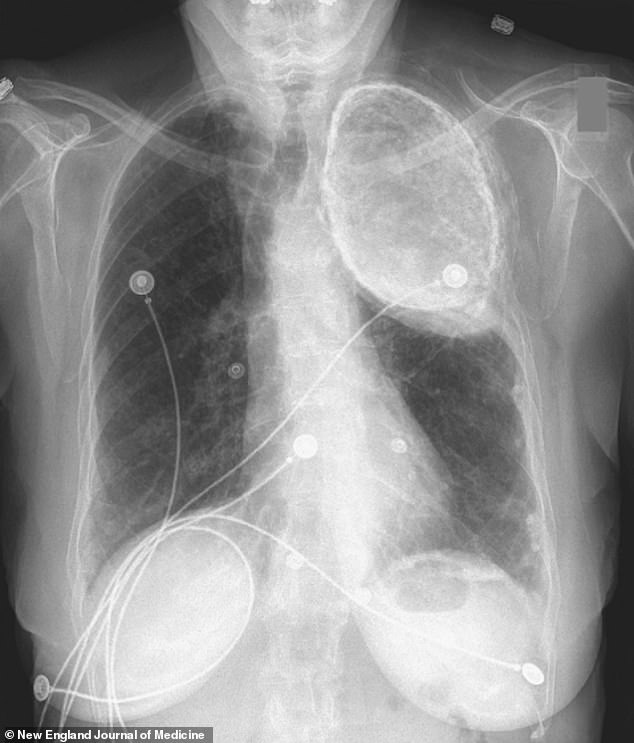

As she received treatment for acid reflux, a condition where stomach acid flows back into the esophagus, doctors also conducted a chest x-ray, revealing a football-shaped cloudy mass in the upper left lobe of her chest.

At that time, the woman had undergone an oleothorax, a previously used treatment where physicians would inject mineral oil into the region surrounding the lungs, known as the pleural space, in order to collapse a section of the lung.

Physicians commonly employed paraffin oil, sourced from petroleum, or vegetable oil to remove oxygen from Mycobacterium tuberculosis, the bacterium responsible for TB, and prevent dormant TB from becoming active again.

Before the availability of antibiotics, individuals who underwent oleothorax treatment would usually have the oil removed once they had recovered from tuberculosis, although some patients, such as the woman described in the case study, retained it for many years.

The individual mentioned in the case study experienced no issues related to the oleothorax or tuberculosis.

Dr. Ghali stated, “The human body is truly remarkable, having adapted and survived with this for approximately 60 or 70 years, and this was merely an unexpected discovery.”